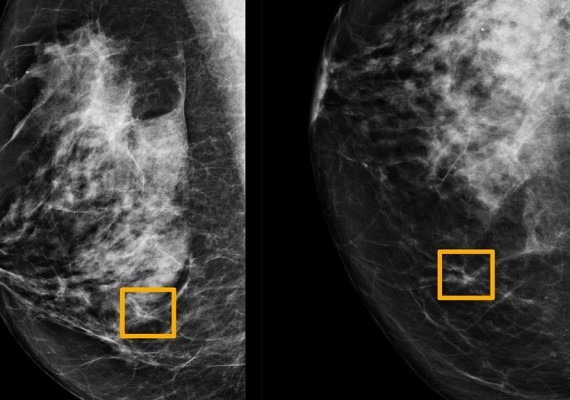

A Google artificial intelligence system was as good as expert radiologists at discovering which women had breast cancer in a new study. The system made the findings from thousands of mammogram images, researchers in the United States and Britain reported. This is the newest study to show that artificial intelligence, or AI, may improve the accuracy of mammograms. Breast cancer affects one in eight women around the world. The study was published in the journal Nature. The American Cancer Society says radiologists miss about 20 percent of breast cancers in mammograms. And many women who get the tests have a false positive result at some point. A false positive result shows a woman with cancer even though she does not have it. The findings of the study were developed with DeepMind AI, which joined with Google Health in September.